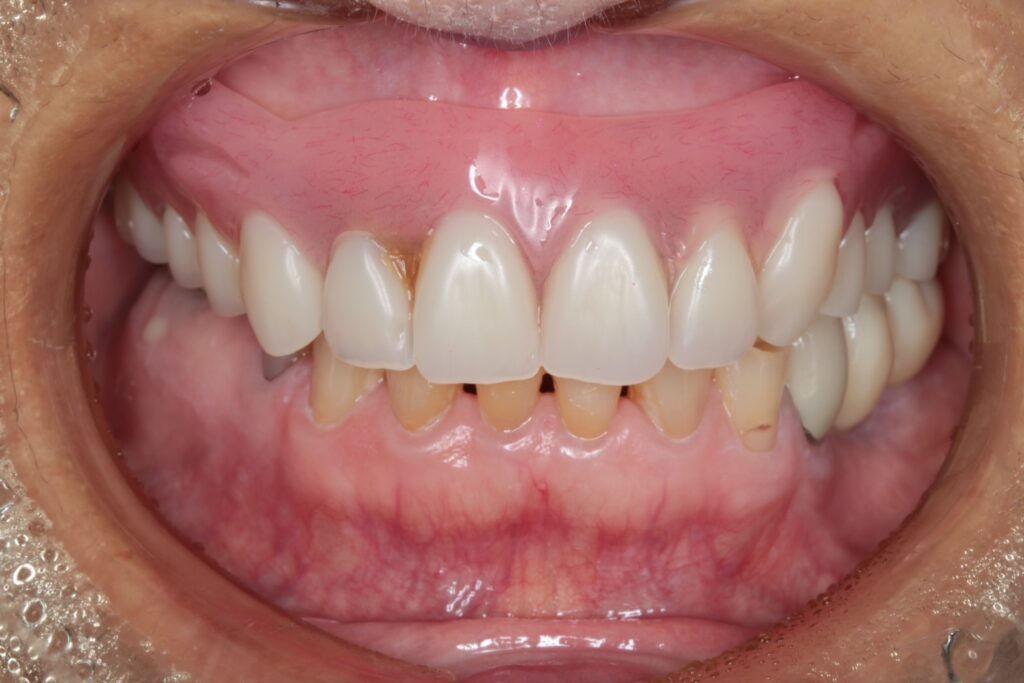

■術後の状態

治療後の写真を見ると、上下ともに大きく審美性が改善し、笑顔の印象も自然になりました。

また、噛み合わせも安定し、患者さまからは「噛めるようになって本当に嬉しい」とのお声をいただきました。